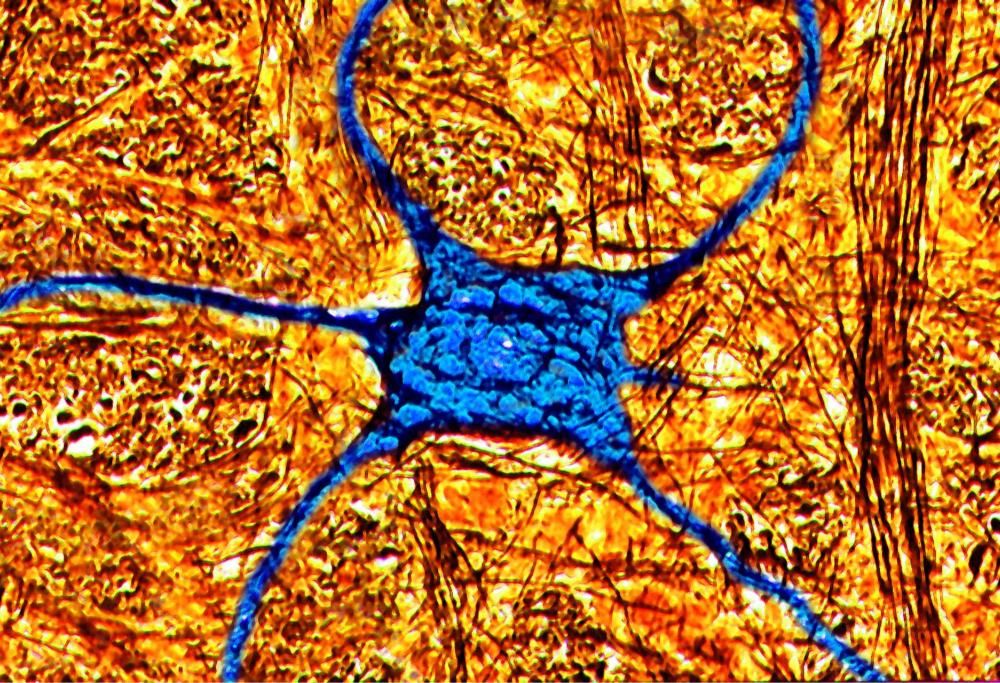

Attraverso uno “scan” del cervello, oggi, è possibile capire se il paziente potrebbe avere o meno tendenze suicide.

I risultati sono stati interessati, attraverso le osservazioni è stato possibile notare come, effettivamente, il nostro cervello reagisca in maniera differente a parole diverse: per ogni parola, infatti, i neuroni seguivano percorsi totalmente differenti.